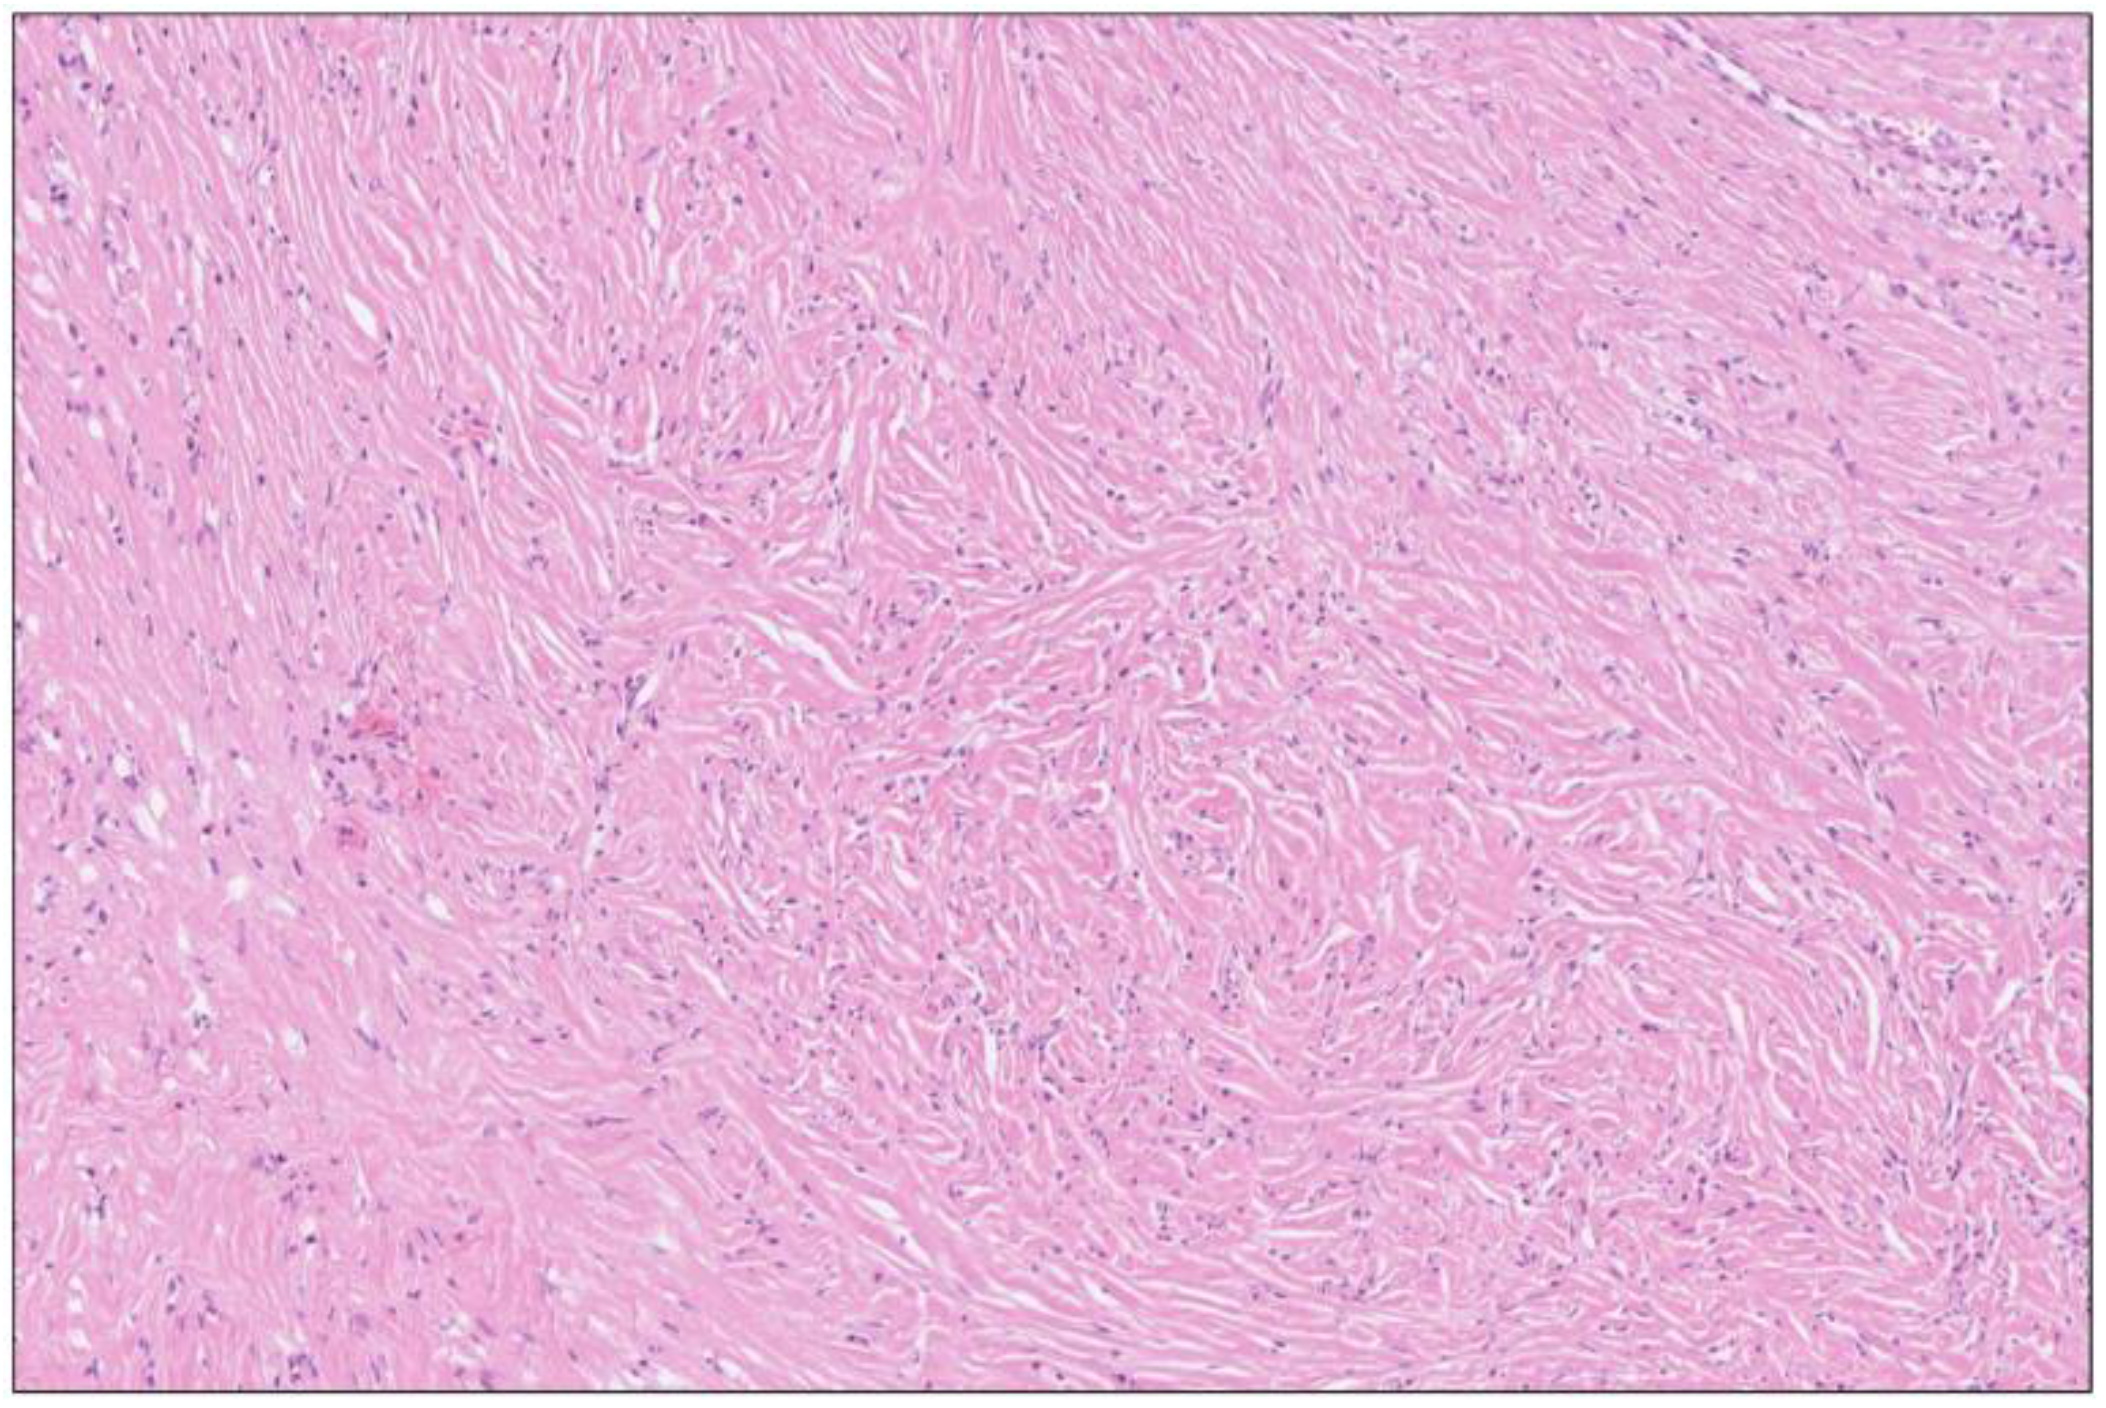

Figure 8. Storiform fibrosis of pancreatic parenchyma close to the cyst wall in Figure 3 and Figure 6 showing a cartwheel arrangement with radiating collagen fibers. H&E staining, 8×.